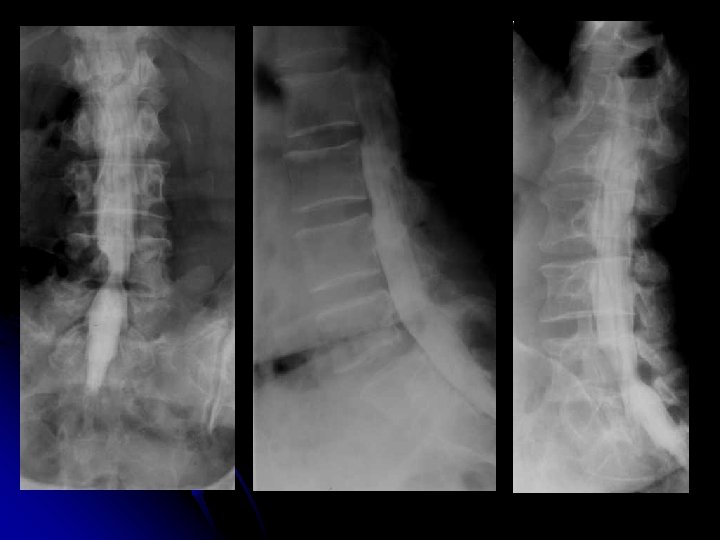

MYELOGRAPHIE l opacification des espaces sous arachnoïdiens l produit de contraste non ionique l Examen invasif: milieu neurochirurgical l Précaution: l Asepsie l Deux clichés du rachis lombaire de face et de profil l Prélèvement du LCR: étude cyto-chimique.

DISCOGRAPHIE lombaire+++

DISCOGRAPHIE